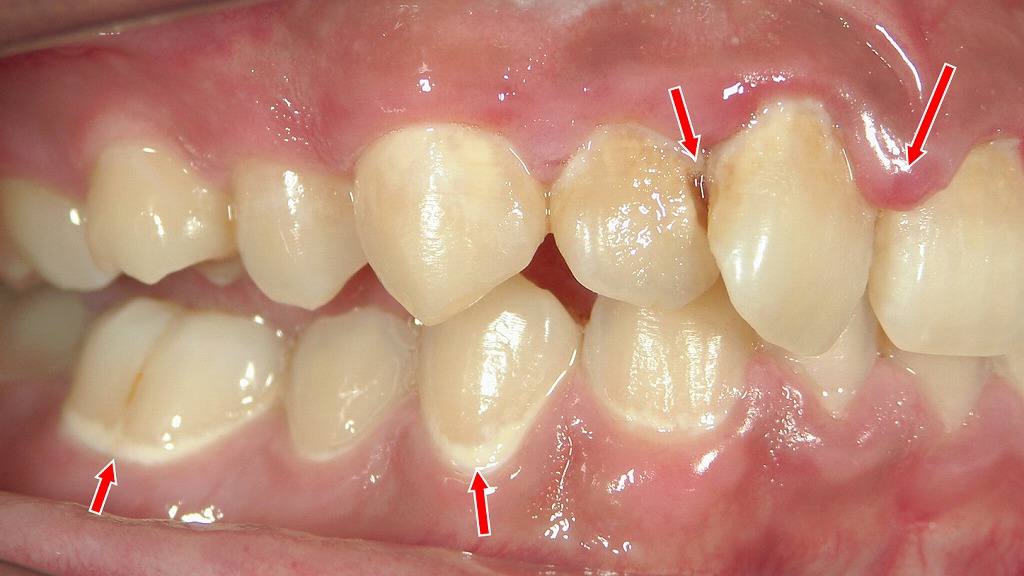

赤い矢印で示す部位は、前歯を中心に広がる初期〜進行した虫歯と歯肉炎の所見です。甘い清涼飲料水やスポーツドリンクを頻繁に摂取する「ペットボトル症候群」では、口腔内が長時間酸性環境となり、歯の表面が脱灰されやすくなります。その結果、歯の根元(歯頸部)や歯と歯の境目に虫歯が多発しやすく、同時に歯肉の炎症も起こりやすくなります。飲み物の種類や飲み方を見直すことが、虫歯予防の重要なポイントです。

この写真には、砂糖入り飲料を日常的に摂ることで起こる典型的な口腔リスクが複数確認できます。

◆ ① プラーク(細菌の塊)が歯面にべったり付着

赤矢印の部分には、白っぽく膜のように見えるプラークが残っています。

清涼飲料水を頻繁に口にすると、口腔内は長時間「糖+酸」にさらされ、プラーク内の細菌活動が活発になり、

- 酸産生の増加

- 歯の脱灰(溶ける)

- 歯肉の炎症悪化

が起こりやすくなります。

◆ ② 歯肉炎〜歯周病のサイン

歯ぐきは赤みを帯び、丸く腫れています。

これはプラークに含まれる細菌により引き起こされる歯肉炎で、放置すると歯周病へ進行します。

ペットボトル症候群の人は、飲み物を頻繁に摂る分だけ、清掃が不十分になりやすく、歯茎の炎症が慢性化します。

◆ ③ 酸に弱くなった歯面に虫歯リスク

矢印で示した前歯表面には、

白濁(脱灰)や褐色の虫歯初期病変が見られます。

ペットボトル症候群では、

- 飲料の糖による酸産生

- 飲料そのものの酸性

- 飲み続けることで口内が常に酸性に傾く

という「二重の酸ストレス」により、虫歯が急速に進行しやすい状態になります。

細かいスナックや清涼飲料を常飲する人に典型的な所見です。

◆ ④ 歯肉近くの歯面の荒れ(酸蝕・歯磨き過多含む)

前歯歯肉付近に見られる茶色い変色や表面のざらつきは、

酸蝕症+プラークの褐色着色が混在している可能性が高い所見です。

清涼飲料水に含まれるクエン酸や炭酸によってエナメル質が軟化すると、ブラッシングによる摩耗も受けやすくなります。